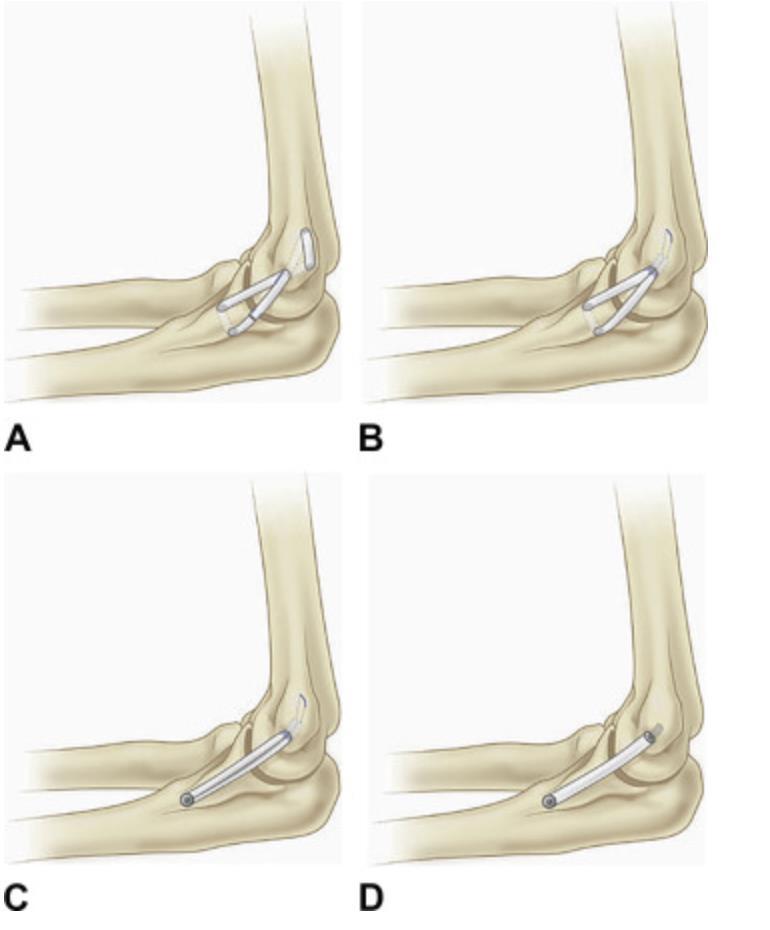

Tommy John Surgery: UCL anterior band ligament reconstruction for high-level throwers that want to continue competitive sports. 90% return to preinjury levels.

complication? Transient ulnar nerve neuropraxia remains the most common complication following medial ulnar collateral ligament (MUCL) reconstruction. The ulnar nerve is found between the FCU and FDP muscles in the forearm.

The docking technique for ulnar collateral ligament reconstruction (UCLR) has been shown to have higher rates of return to play and a lower risk of complications when compared to the original Jobe technique. Illustration A shows four commonly used UCLR techniques including (A) Jobe Technique, (B) Docking technique, (C) The David Altchek, Neal ElAttrache Tommy John technique, and (D) Dual Interference Screw technique.